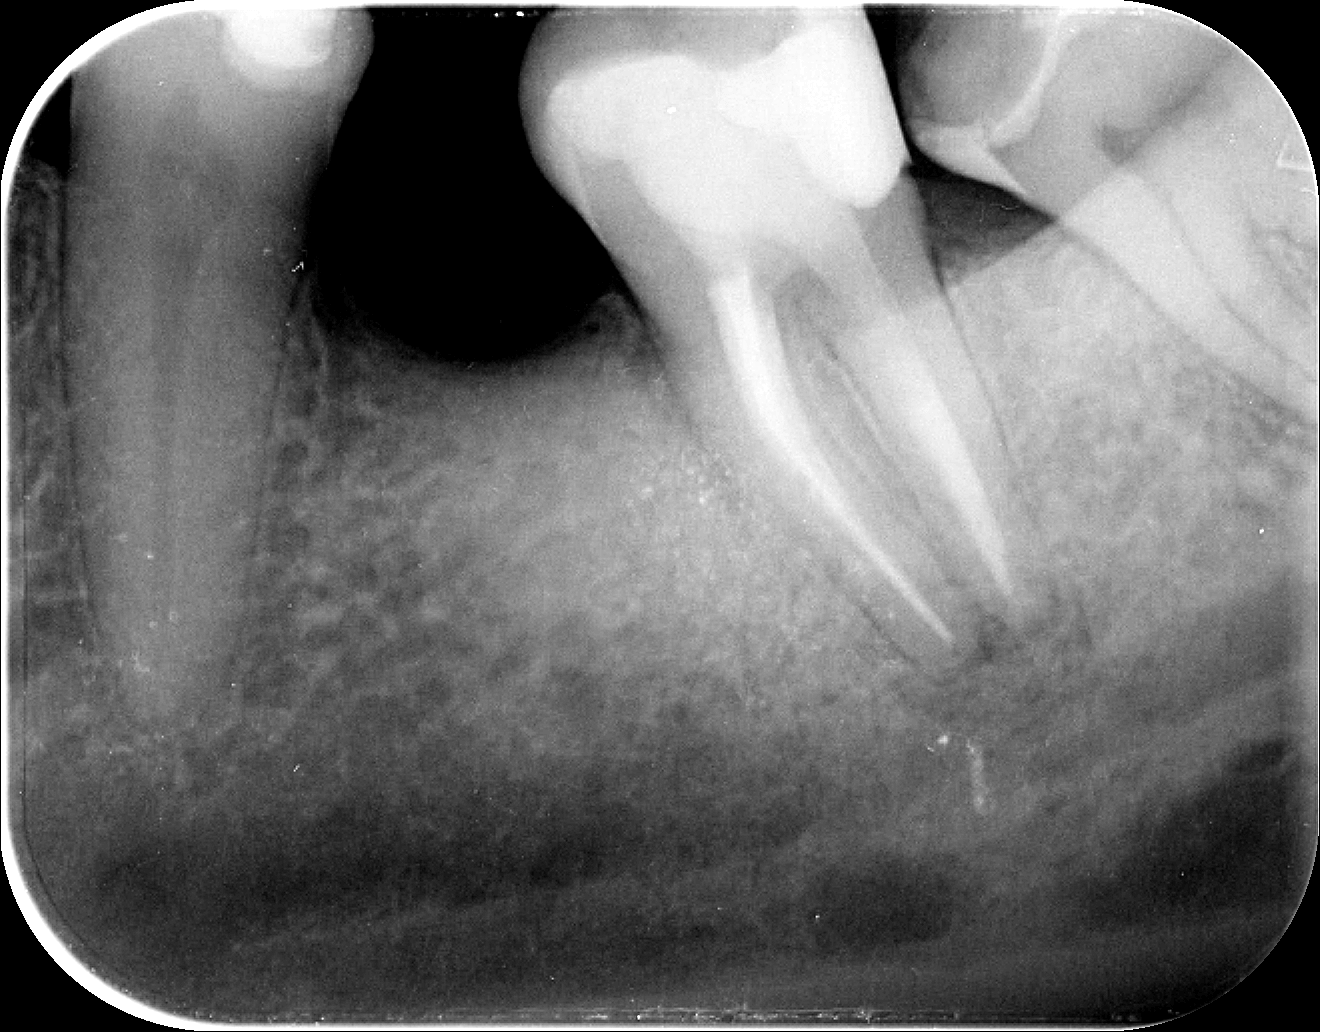

A következő felvétel már a kezelés utáni kontrollon készült. A kezelőorvos elégedetten állapíthatja meg, hogy a gyulladás múlóban van, és hamarosan nyoma sem lesz.

A kontrollon a fogszakorvos azt is megvizsgálja, hogy a kezelés óta mi változott, és ha valami nem a kívánt irányba mutat, akkor megteszi a szükséges intézkedéseket, illetve felvértezi Önt jó tanácsokkal.